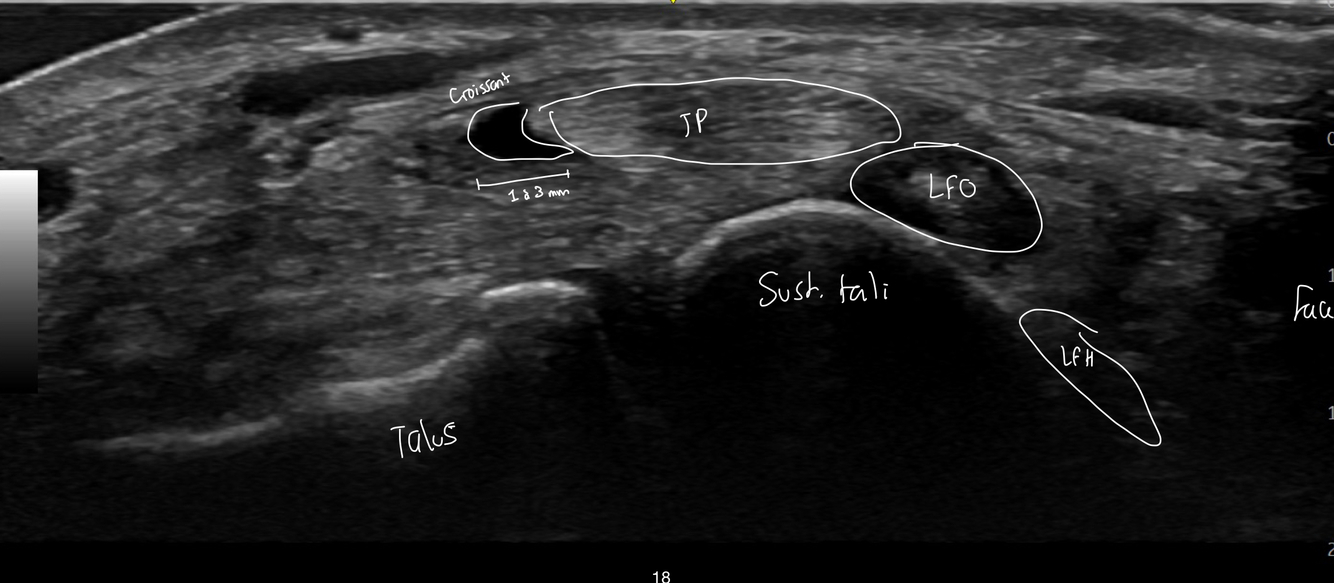

Identifie les structure sur l’image

Dites dans quelle region du pied il se situe

A

Nous sommes en médial de la cheville

C’est écrit talus, mais c’est le tibia à gauche